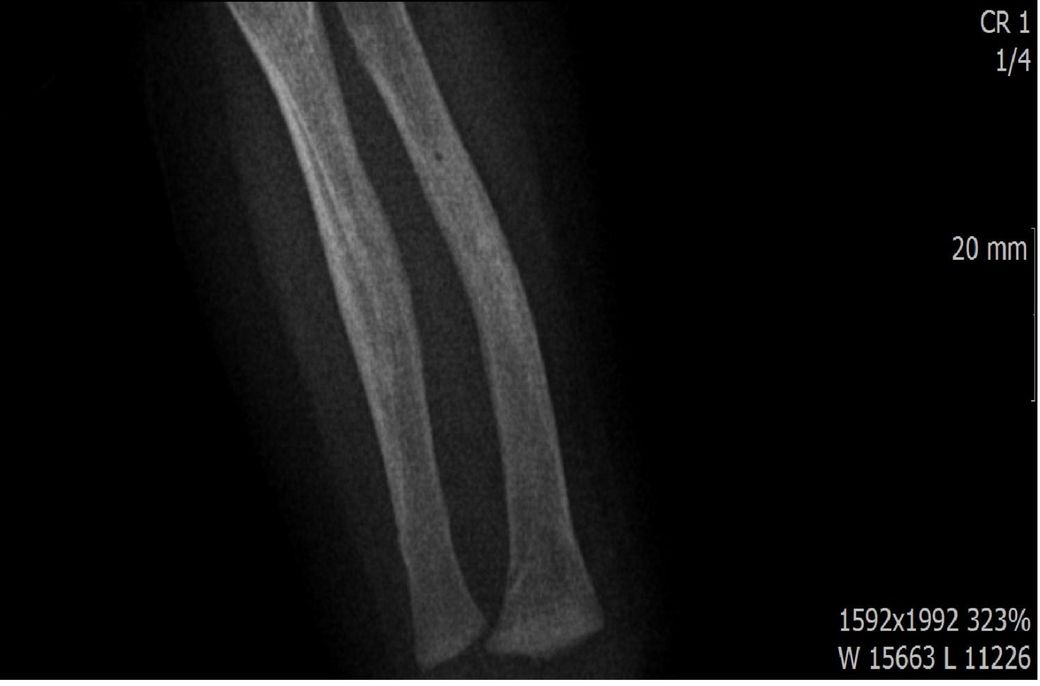

다름이 아니라, 첨부드린 엑스레이(X-ray) 사진처럼 골절 사실을 알게 되고 골절 발생 시점 대략적으로나마 추정시기를 파악하려고 문의 드리게 되었습니다

1) 3월 30일 촬영한 X-ray만으로 정확한 골절 시기를 100% 특정하는 데에는 한계가 있다는 점 충분히 인지하고 있기에 촬영날짜 기준으로 대략적으로 어느정도 시점에서 발생되었을 것으로 추측(ex 당일, 7~10일전, 7~14일 전, 10일 ~ 20일전, 14일 ~ 30일전 등등등)되는지 이해하고 싶습니다.

• 2번 째 사진

엑스레이 만으로 골절 발생 시기를 정확히 특정하긴 어렵지만 뼈의 염증 반응, 골막 반응, 골흡수 신생 정도를 통해 대략 추정은 가능합니다. 보통 급성 골절은 1~7일 이내, 골절선이 희미해지고 골막 반응이 보이면 10~20일 전후 뼈 융합이 일부 보이면 3~4주 이상 경과로 추정할 수 있습니다. 3월 30일 촬영 기준, 골절선의 형태와 신생골 유무에 따라 7~21일 내외의 외상으로 판단되는 경우가 많아요!

골절의 정확한 시기를 예측하기는 어려움이 있으나, 뼈의 골절선이 뚜렷하게 관찰된다면 0~7일 이내의 가능성이 있고 흐린 가골이 관찰되거나 골막의 일부 반응이 관찰된다면 7~14일 이내, 가골이 형성중인것이 관찰된다면 2-3주 이상의 골절시기를 대략적으로 유추해볼 수 있습니다.

골절의 상태를 보고 골절선이 선명하고 부위에 가골이 형성되지않았다면 보통 일주일 이내, 골절선이 보이지만 주변 부위에 가골이 조금씩 있다면 2주 이내, 골절선이 잘안보이고 가골이 보인다면 한달 이내로 판단 할 수 있습니다.

지금과 같이 엑스레이상 골절이 잘 보이는것으로 보아 2주 이내에 특별한 이슈가 있을만한지 생각해보시길 바랍니다^^